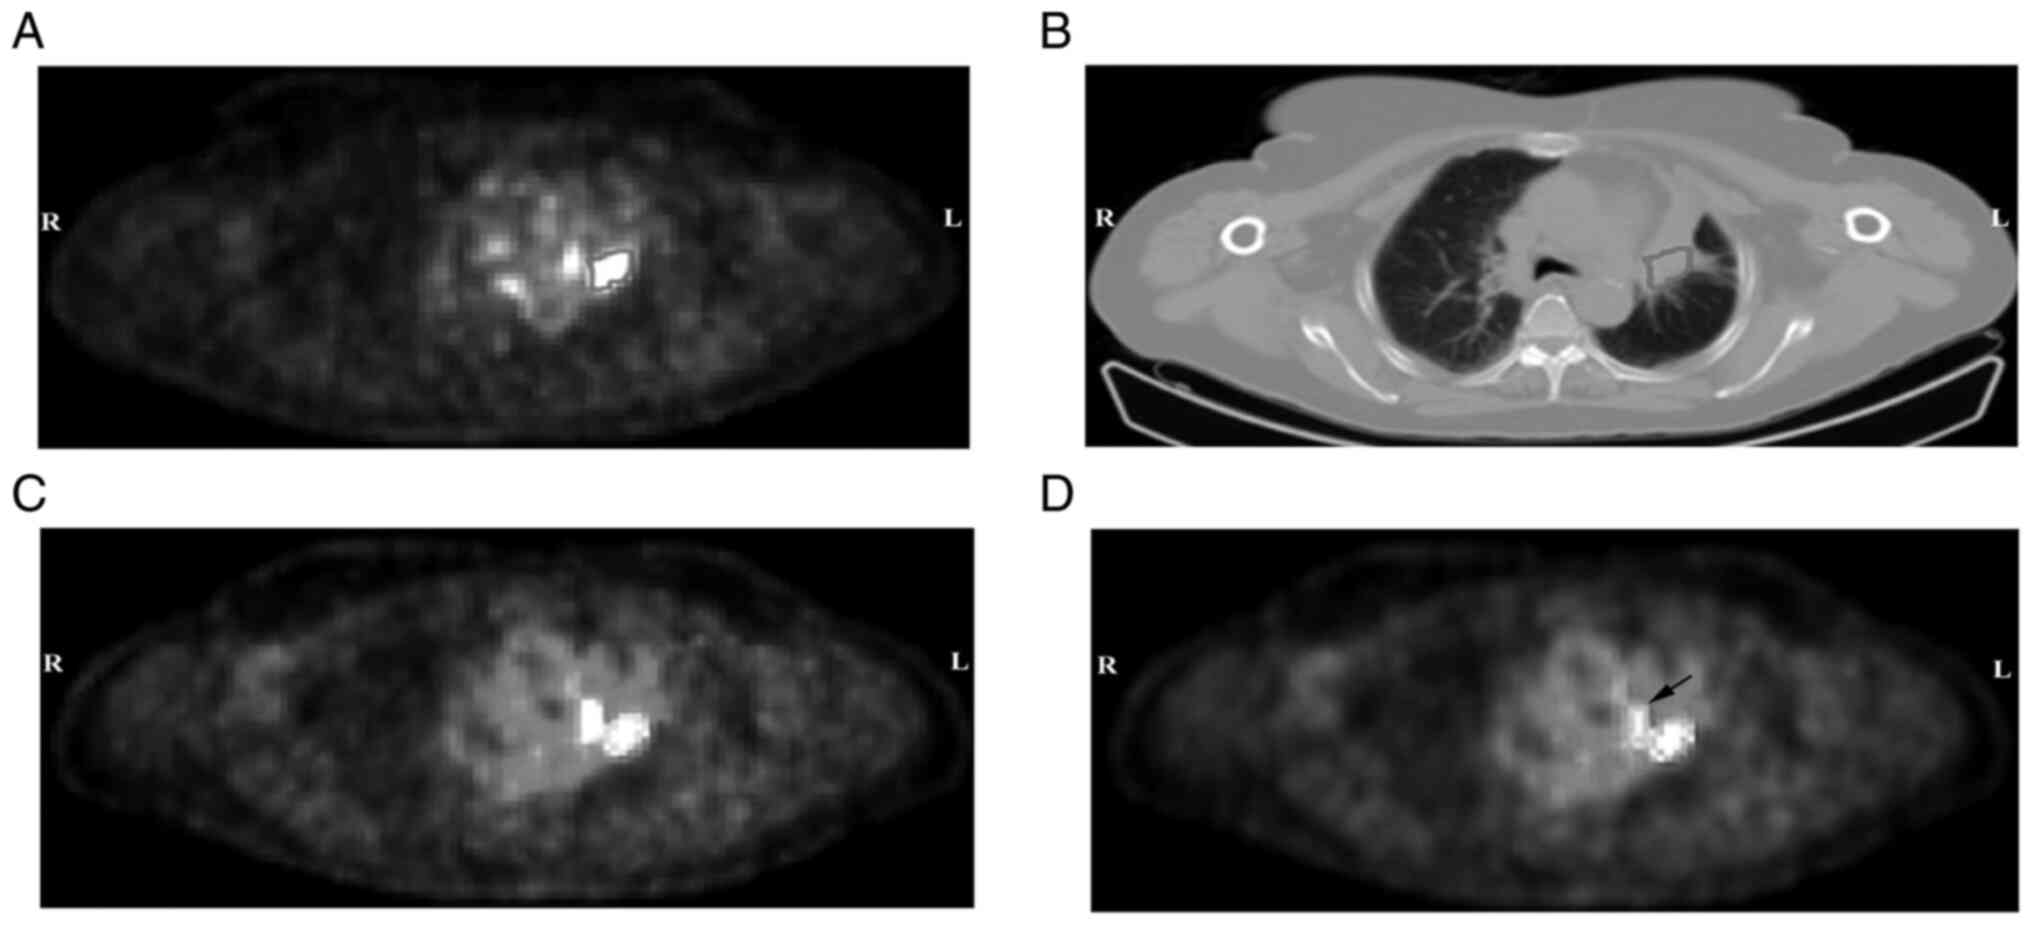

Recurrence patterns are significantly associated with the 18F‑FDG PET/CT radiomic features of patients with locally advanced non‑small cell lung cancer treated with chemoradiotherapy

A model for predicting the recurrence pattern of patients with locally advanced non‑small cell lung cancer (LA‑NSCLC) treated with chemoradiotherapy is of great importance for precision treatment. The present study analyzed whether the comprehensive quantitative values (CVs) of the fluorine‑18(18F)‑fluorodeoxyglucose (FDG) positron emission tomography (PET)/computed tomography (CT) radiomic features and metastasis tumor volume (MTV) combined with clinical characteristics could predict the recurrence pattern of patients with LA‑NSCLC treated with chemoradiotherapy. Patients with LA‑NSCLC treated with chemoradiotherapy were divided into training and validation sets. The recurrence profile of each patient, including locoregional recurrence (LR), distant metastasis (DM) and both LR/DM were recorded. In the training set of patients, the primary tumor prior radiotherapy with 18F‑FDG PET/CT and both primary tumors and lymph node metastasis were considered as the regions of interest (ROIs). The CVs of ROIs were calculated using principal component analysis. Additionally, MTVs were obtained from ROIs. The CVs, MTVs and the clinical characteristics of patients were subjected to aforementioned analysis. Furthermore, for the validation set of patients, the CVs and clinical characteristics of patients with LA‑NSCLC were also subjected to logistic regression analysis and the area under the curve (AUC) values calculated. A total of 86 patients with LA‑NSCLC were included in the analysis, including 59 and 27 patients in the training and validation sets of patients, respectively. The analysis revealed 22 and 12 cases with LR, 24 and 6 cases with DM and 13 and 9 cases with LR/DM in the training and validation sets of patients, respectively. Histological subtype, CV2‑5 and CV3‑4 were identified as independent variables in the logistic regression analysis (P<0.05). In addition, the AUC values for diagnosing LR, DM and LR/DM were 0.873, 0.711 and 0.826, and 0.675, 0.772 and 0.708 in the training and validation sets of patients, respectively. Overall, the results demonstrated that the spatial and metabolic heterogeneity quantitative values from the primary tumor combined with the histological subtype could predict the recurrence pattern of patients with LA‑NSCLC treated with chemoradiotherapy.